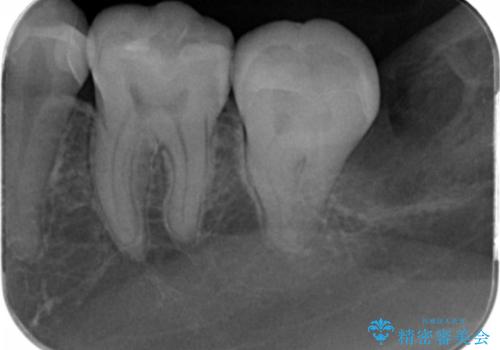

- 定期検診で来院してレントゲンを撮ったところ

歯と歯の間にう蝕ができていました。

拡大鏡下でう蝕を全て除去してe-maxインレーにて治療を行いました。